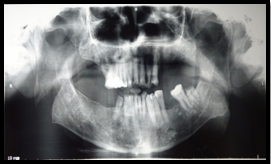

A 65 year old male patient reported to the outpatient department of Periodontology, SGT Dental College, Budhera with the chief complaint of bleeding gums, mobility of teeth and difficulty in mastication since one month. Patient also complains pain in relation to right back tooth region for 2 weeks. Pain was sharp in nature, aggravated on lying down, relieved by taking medication and was not referring to any other site. Patient gave past medical history of PCV since 2003 and on being medications for the same which included: Hydroxyurea- 500 mg twice daily as cytoreductive agent to decrease the leukemogenic risk and ecosprin -75 mg (low dose aspirin) to lessen the risk of thrombosis in an artery. Cimetidine was given (H2 receptor antagonists) to relieve gastrointestinal symptoms of peptic ulceration. Citrezine (antiallergic) was prescribed to relieve generalized itching which patient was suffering from. On intra-oral examination it was found that there was mobility present in relation to all the teeth, red inflammed gingiva with loss of stippling which bled profusely on slight provocation, generalized recessiongingival enlargement present in relation to all the teeth, attrition and root caries present in relation to 45. Patient was advised Orthopantogram (OPG) which showed generalized horizontal bone loss extending upto two third of root surface of almost all the teeth present (Figures 1&2).

Figure 1 Intra- oral photograph. .